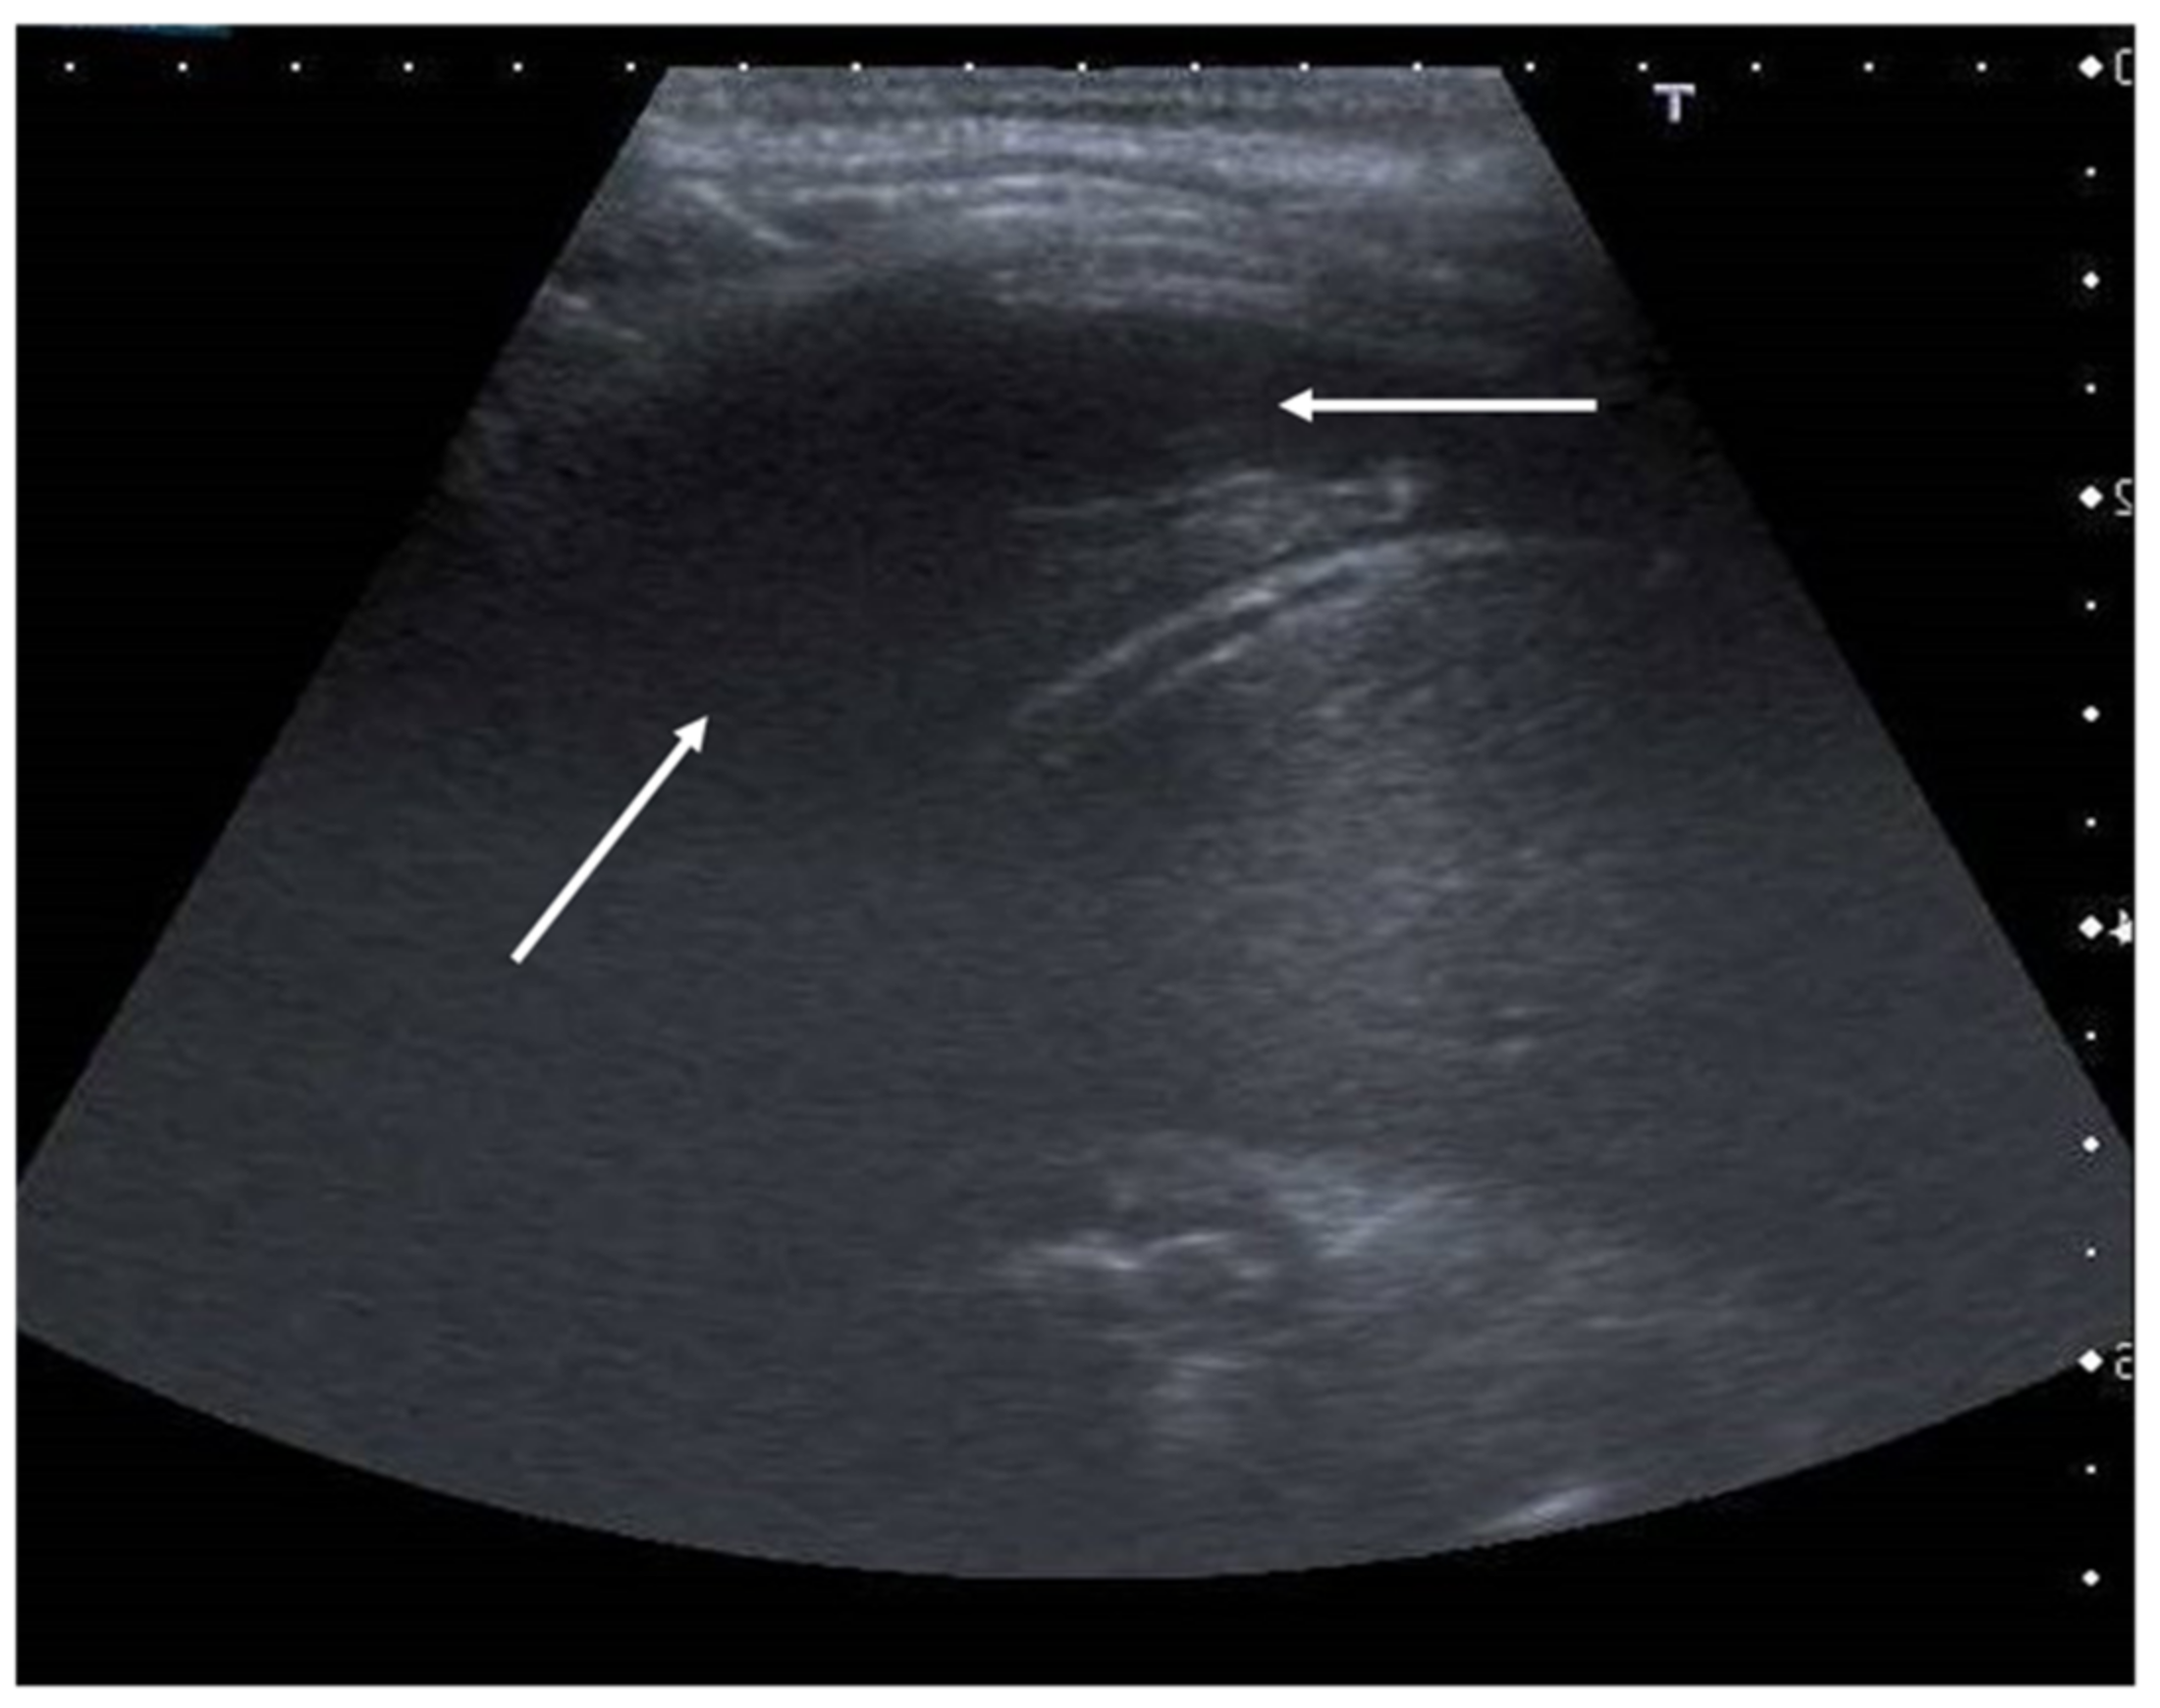

8. Pneumothorax, Pleural Effusion Empyema and Lung Abscess

- Grimberg, A.; Shigueoka, D.; Atallah, A.N.; Ajzen, S.; Iared, W. Diagnostic accuracy of sonography for pleural effusion: Systematic review. Sao Paulo Med. J. 2010, 128, 90–95. [Google Scholar] [CrossRef] [Green Version]

- Soni, N.J.; Franco, R.; Velez, M.I.; Schnobrich, D.; Dancel, R.; Restrepo, M.I.; Mayo, P.H. Ultrasound in the diagnosis and management of pleural effusions. J. Hosp. Med. 2015, 10, 811–816. [Google Scholar] [CrossRef] [PubMed] [Green Version]

- Prina, E.; Torres, A.; Carvalho, C. Lung ultrasound in the evaluation of pleural effusion. J. Bras. Pneumol. 2014, 40, 1–5. [Google Scholar] [CrossRef] [Green Version]

- Calder, A.; Owens, C.M. Imaging of parapneumonic pleural effusions and empyema in children. Pediatr. Radiol. 2009, 39, 527–537. [Google Scholar] [CrossRef]

- Svigals, P.; Chopra, A.; Ravenel, J.; Nietert, P.J.; Huggins, J.T. The accuracy of pleural ultrasonography in diagnosing complicated parapneumonic pleural effusions. Thorax 2017, 72, 94–95. [Google Scholar] [CrossRef] [Green Version]